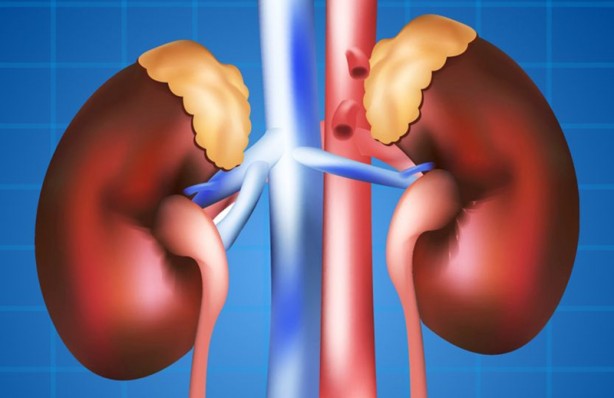

Şişlik, baş ağrısı ve hatta yorgunluk... Vücuttaki bütün sistemleri etkileyen böbreklerdeki küçük bir sorun bile birçok farklı belirtiyle neden olabilir. İşte böbrek problemlerini gösteren işaretler.